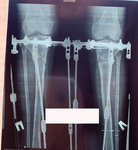

Дата операции - 17.10.2019г

Дата снятия аппаратов - 14.02.2020

Срок сращения - 117 дней.